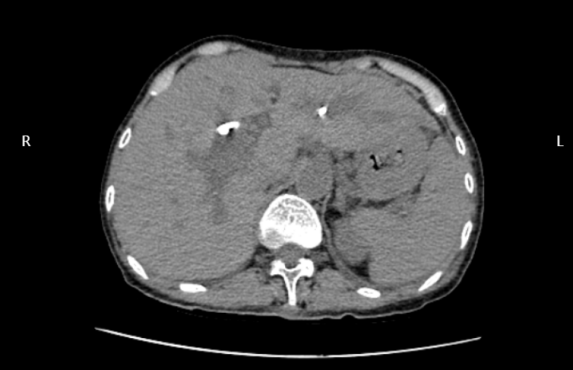

術(shù)后CT顯示引流管準(zhǔn)確置入擴(kuò)張的膽管